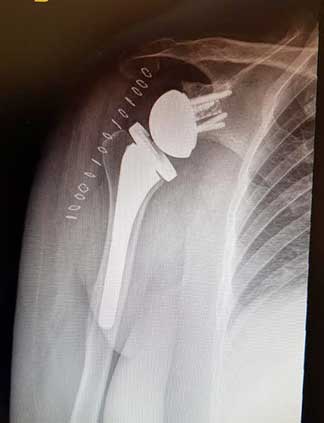

Prótesis de hombro

Es la sustitución artificial de la articulación por un implante de metal y polietileno indicada por artrosis, desgaste o lesión masiva del manguito rotador.

La razón más frecuente es aliviar el dolor intenso causado por artrosis, corregir las deformidades angulares en varo, valgo y contractura en flexión en adultos mayores y para adultos jóvenes, está indicada en lesiones crónicas articulares que ocasionan un desgaste acelerado.

Resultados esperados

La recuperación de la cirugía reemplazo de hombro con una prótesis reversa de hombro o una prótesis anatómica de hombro va muy ligada al estado de la articulación previamente lesionada y al apego que tenga el paciente con la terapia física y así poder ofrecer una recuperación buena, muy buena o excelente.